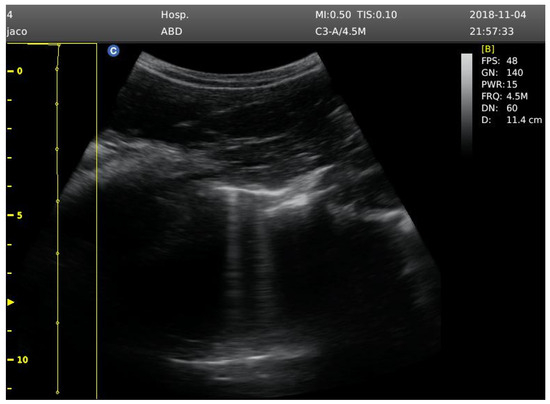

Four participants showed signs of mild pulmonary edema, after diving, coinciding in both protocols (Supplementary Materials Table S1). The ultrasound B-lines count was recorded at baseline, 10 min post-immersion, and at 1 h post-immersion (Figure 1).

Figure 1.

Signs of ultrasound B-lines. Image analyzed at 12 cm depth.

Baseline ultrasound B-lines were recorded before the competition, with participants not having conducted diving activity 24 h before the assessment. Lung ultrasound was collected in the seated position by displaying mode B, using 2D ultrasonic imaging, with a convex transducer 3.5 MHz (Chison ECO 5 Portable Ultrasound Scanner, Wuxi, China). Bilateral imaging of the hemithorax from the second to fourth intercostal spaces was performed, culminating in 6 assessment zones.

A B-line was detected as an echogenic comet-shaped signal spreading from the pleural line to the further border of the screen. The same medical researcher (E-P) performed all ultrasound measurements; then, B-lines were analyzed by another medical researcher specialist on pulmonary ultrasound (J-L) to provide a total B-line score [14]. Ultrasound B-lines are an index of extravascular lung fluid, and the sensitivity and reliability of this method have been contrasted in different studies compared with radiographic imaging [15,16]. After analysis, the total number of B-lines was recorded to detect possible signs of pulmonary edema.